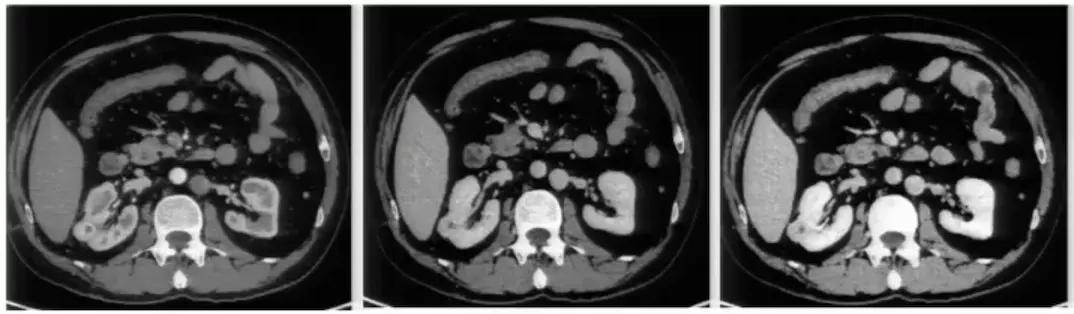

图1:腹膜后方下腔静脉处于腹主动脉左侧;左肾静脉出左肾门后,汇入下腔静脉路径缩短

肾癌伴血管结构畸形

肾癌伴血管结构畸形患者的血管结构畸形往往容易被忽视。 在手术的过程中,如不注意就可能造成肝右叶血流的回流障碍,导致严重的临床后果。